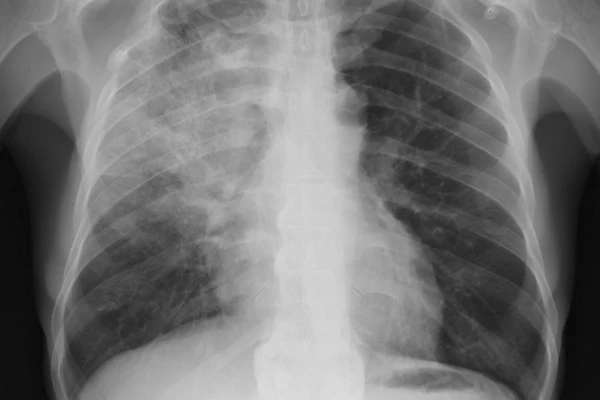

Симптомы

Начальную стадию респираторной пневмонии сложно диагностировать. В основном это связано с тем, что пациент находится без сознания и дышит не самостоятельно, а с помощью аппарата. У больного нет явных проявлений пневмонии: нет кашля, мокроты и общих симптомов. Течение такой пневмонии становится «скрытым».

Общая воспалительная реакция, которая при других пневмониях играет роль индикатора патологического процесса (повышение температуры тела, лейкоцитоз, трабекулярный сдвиг лейкоцитарной структуры, увеличение СКВ, белков острой фазы), регистрируется до развития ВАП. и не всегда имеет диагностическое значение.